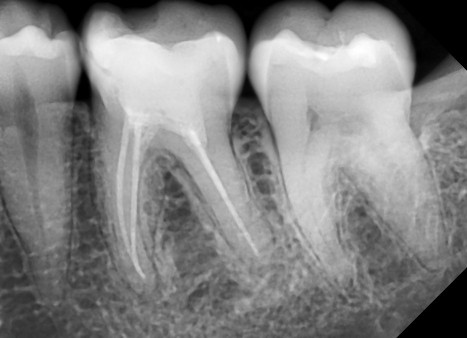

Medicul va determina exact prezenţa cariilor, infecţiilor, pungilor parodontale, fracturilor sau chisturilor, ca zone închise la culoare acolo unde nu ar trebui să fie.

- Carii incipiente, ce pot fi tratate foarte uşor

- Amploarea reală a cariei care la suprafaţă pare mică

- Existenţa unor infecţii dentare

- Carii aflate sub lucrări sau plombe

- Retroalveolară – precisă, dar pentru doar câţiva dinţi